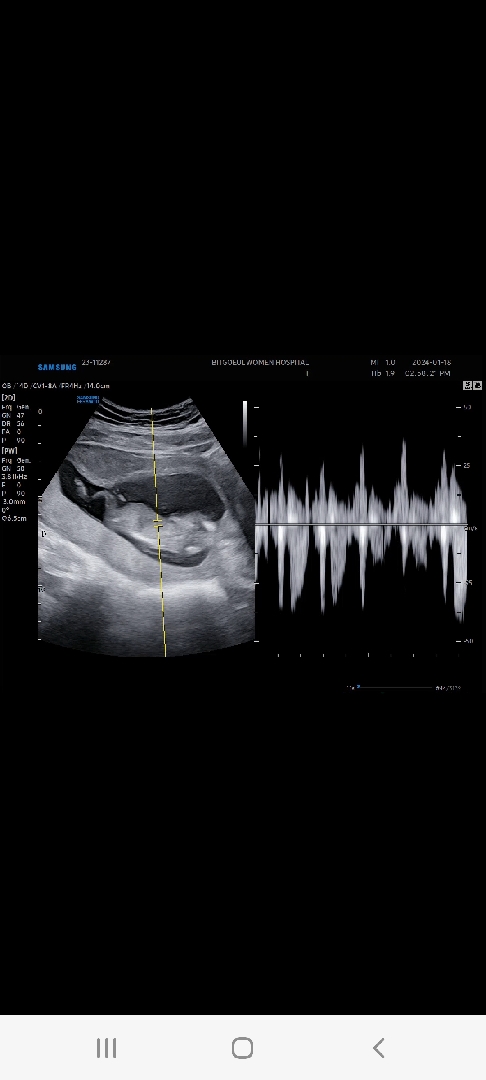

12주3일차 까꿍이

다른분들은 12주차에 5.몇센치전데 애기가 크련지 6.4센치에 날짜도 3일 오버됬네용... 아직까지 체중변화는 없고 배는 조금씩 나오는 것 같아용(지금은 13주 1일차) 저는 매일 양치덧,토덧에 죽겠는데 잘지내는거 보면 대견스럽기도 하면서 넘크게 나올까봐 걱정되기도 해요ㅠㅠ 각도법 보시는 고수님들 아들일까요 딸일까요?